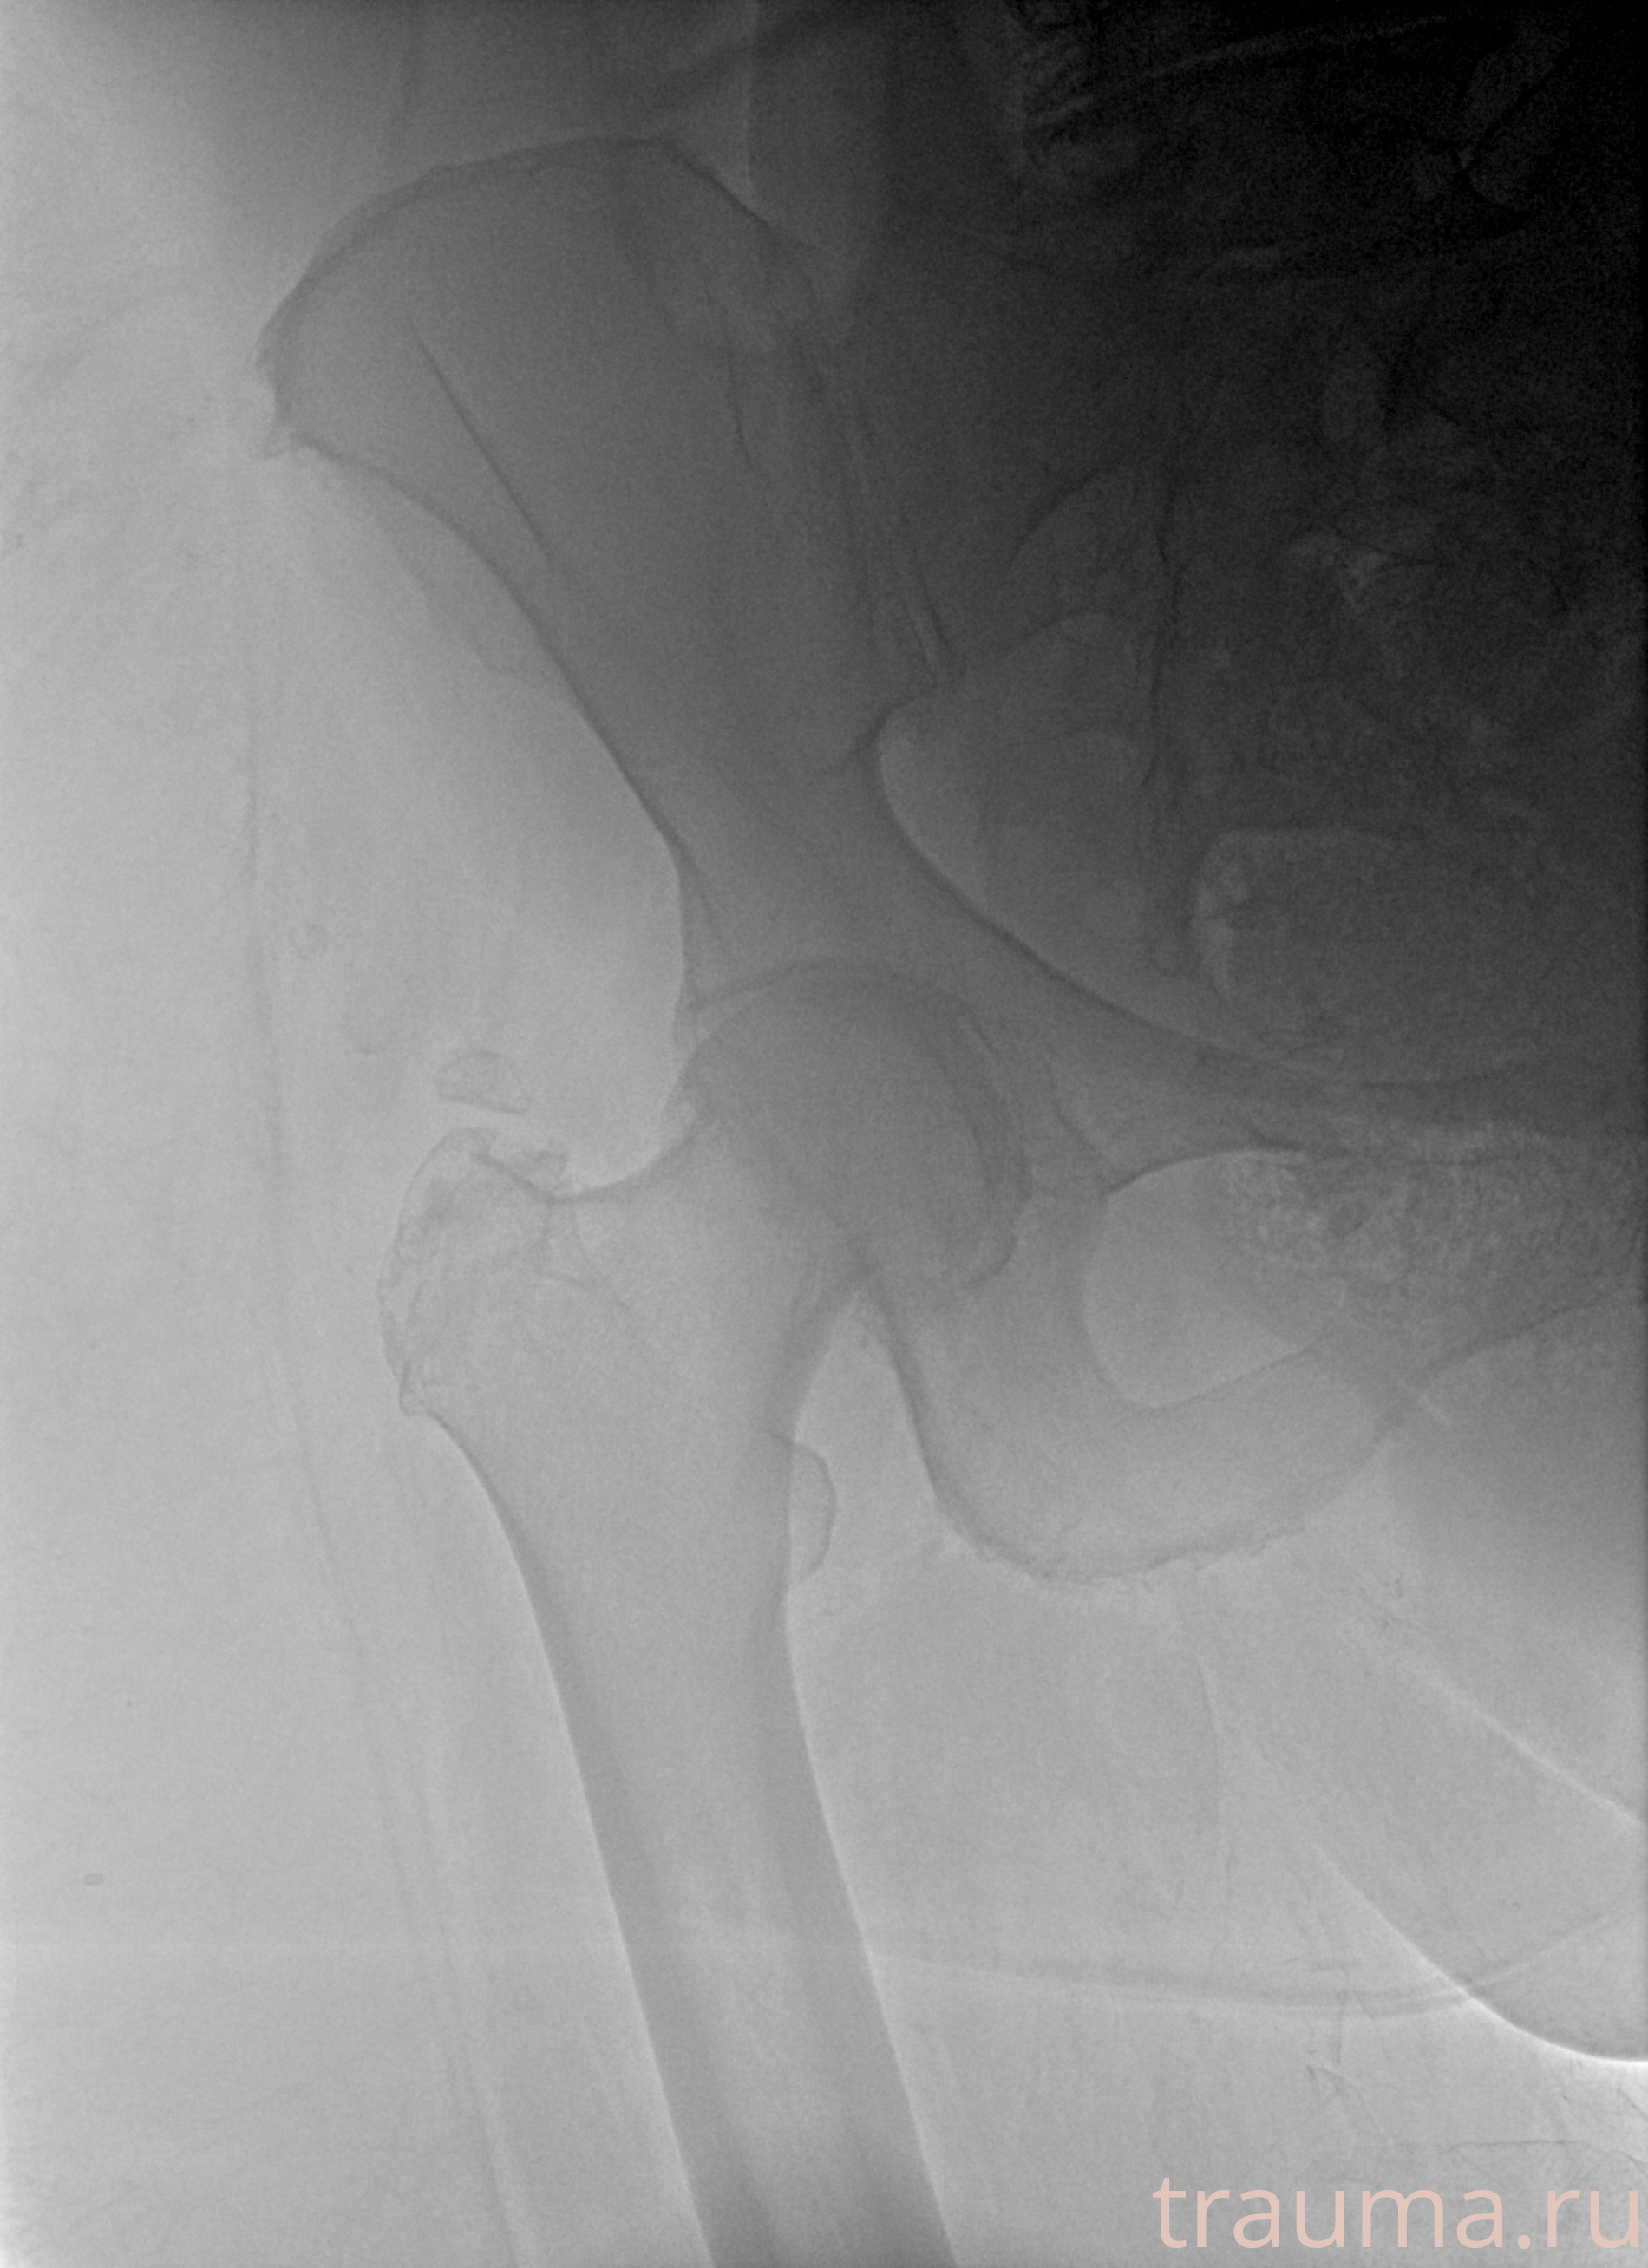

Первая помощь при переломе шейки бедра

Рентгенограммы

Рентген на дому: по вашему адресу приезжает врач-рентгенолог, травматолог-ортопед с мобильным рентгеновским аппаратом, проводит диагностику травмы или заболевания, делает необходимые рентгенограммы, дает рекомендации по дальнейшему лечению. Получить качественные снимки в домашних условиях возможно благодаря уникальной методике, разработанной МосРентген Центром для института  Склифосовского

при переломе шейки бедра и пневмонии от компании МосРентген Центр - партнера Института имени Склифосовского